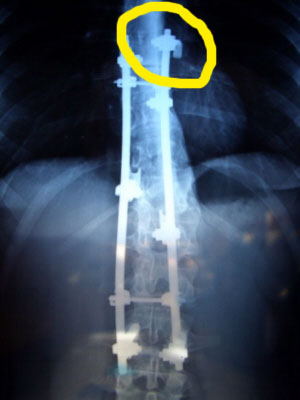

Ich heiße Julia und bin hier neu. Ich freue mich sehr, dass ich solche Forum gefunden habe :). Ich wäre dankbar, wenn Sie mir auf ein paar fragen antworten könnten. Ich hatte Operation vor 1,5 Jahr. Am Anfangt war alles in Ordnung, aber nach einem Monat, als ich zu viel gesessen habe, ist etwas passiert. Es tat mir sehr weh und die Stäben sahen so aus, als sie abhaken könnten.(

Sie können das auf dem ersten Foto sehen.)

Und dann als ich meinen Arzt danach gefragt habe, sagte er, dass ich schmal bin, deshalb ist es so :/. Trotzdem, habe ich die Fotos gemacht. Was finden Sie? Ist es alles in Ordnung oder nicht?

Hallo Julia, ich bin KEIN Spezialist für Operierte, aber ich habe mir Gedanken über Deine Implantate gemacht.

Du bist wegen M. Scheuermann-Kyphose operiert worden.

Ich glaube/vermute, daß Dein Implantat zu KURZ ist!

Es sieht so aus als wärest Du nur von dorsal (von hinten) operiert.

An Deiner Wirbelsäule wurde keine ventrale (bauchseitige) Reklinatios-Spondylodese durchgeführt. Dabei werden die vorhandenen zermürbten Scheuermann-Bandscheiben entfernt und anstatt der Knorpelanteile Knochenstückchen aus einer Rippe, Beckenkamm oder seltener aus dem Wadenbein eingesetzt.

Deine Scheuermann-Kyphose ist noch voll da, wie auf dem Bild zu sehen ist.

Der Typ Implantat, eine Weiterentwicklung des Harringtons neigt zu Brüchen und zum Ausreisen der Pedikelhaken.

Sind die Röntgenbilder gemacht worden NACHDEM Du die Beschwerden hattest oder stammen die von vorher?

Ich meine, daß Du Dich unbedingt mal einem Profi vorstellen solltet, der das ganze mal kritisch begutachtet.

Ich werde Deine Bilder auf jeden Fall am Dienstag nach Ostern Dr. Hoffmann zeigen.

Es wäre gut noch weitere Bilder Deines Rückens sehen zu können, die den gesamten Rücken ( nicht nur kleiner Ausschnitt) von hinten und von der Seite und auch vorgebeugt zeigen.

Ich bin völlig unsicher ob das so in Ordnung ist.

rechter haken

toni und ich haben uns deine bilder nochmals genauer angesehen !

wir sind uns nicht sicher, aber vermuten, daß was mit dem rechten oberen haken nicht stimmt !

Mir scheint, dass auf rechte Seite alles gut ist (Das, was Ihr markiert habt, ist vielleicht der Hacken auf der Rippe). Für mich die linke Seite ist schlechter - mehr "raussteht".

genau das hat toni auch vermutet, der haken greift also doch in die rippe !

Julia, ich denke Toni hat vollkommen recht. Deine Versteifungsstrecke ist zu kurz, und der rechte obere Haken sitzt anscheinend nicht richtig. Links ist die Verankerung schlecht zu beurteilen.

Deine Wirbelsäule hat sich jedenfalls oberhalb der versteiften Strecke sehr stark nach vorn gekrümmt, deshalb sind die Enden der Stäbe jetzt von außen sichtbar.